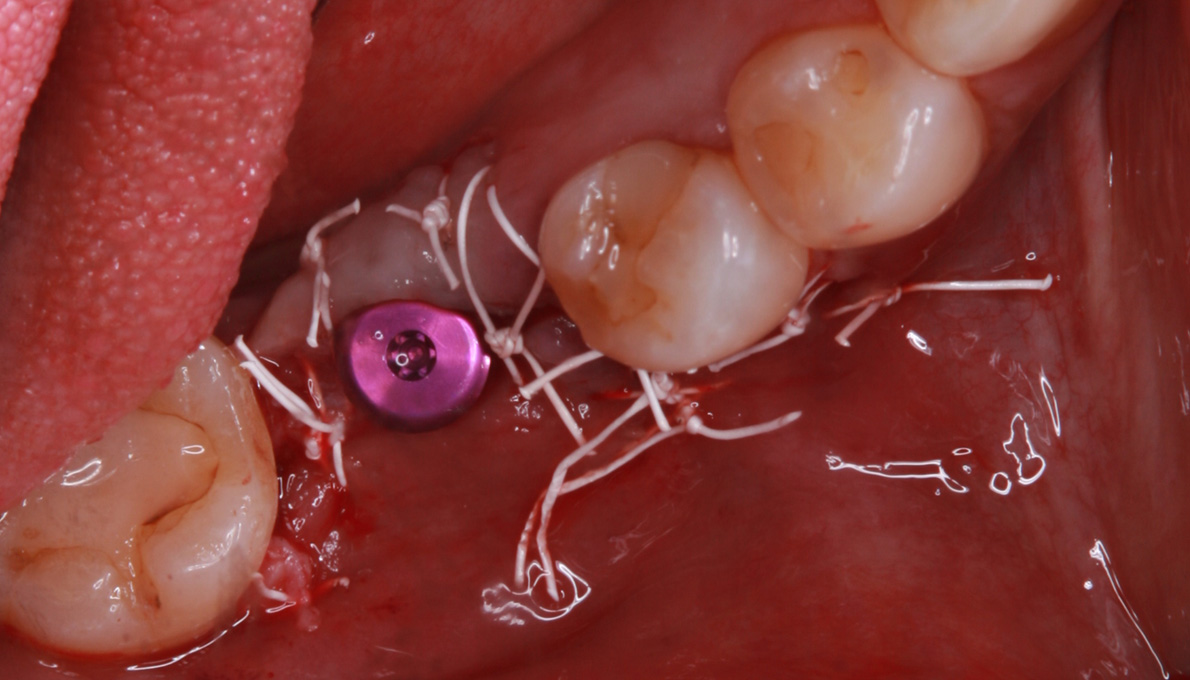

骨移植(人工骨+メッシュプレート)を行い、骨を造りました。

CT画像 -

インプラント手術を行いました。

手術の時に使用するサージカルステント

レントゲン画像 -